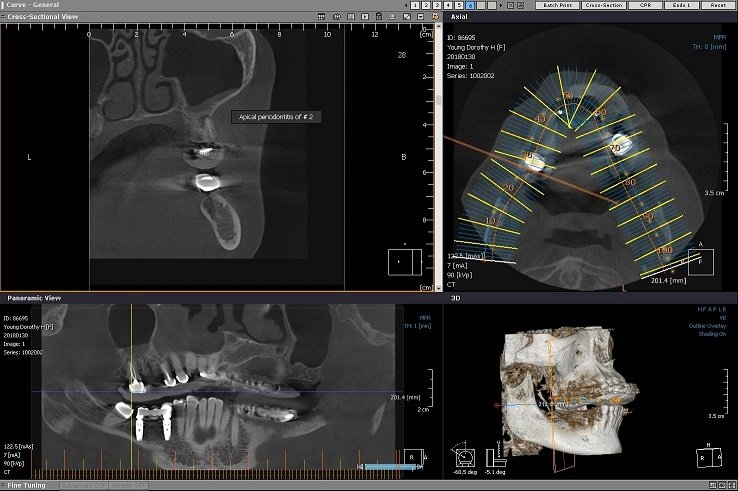

En este video la Dra. Lugo explica las distintas características a evaluar en lesiones para diferenciar aquellas que sugieran Benignidad de Malignidad, como lo son: Tipo de imagen Bordes Tamaño Relación con la cortical adyacente Relación con los dientes adyacentes entre otras. Material de apoyo: Cátedra de Radiología de la Facultad de Odontología de la […]